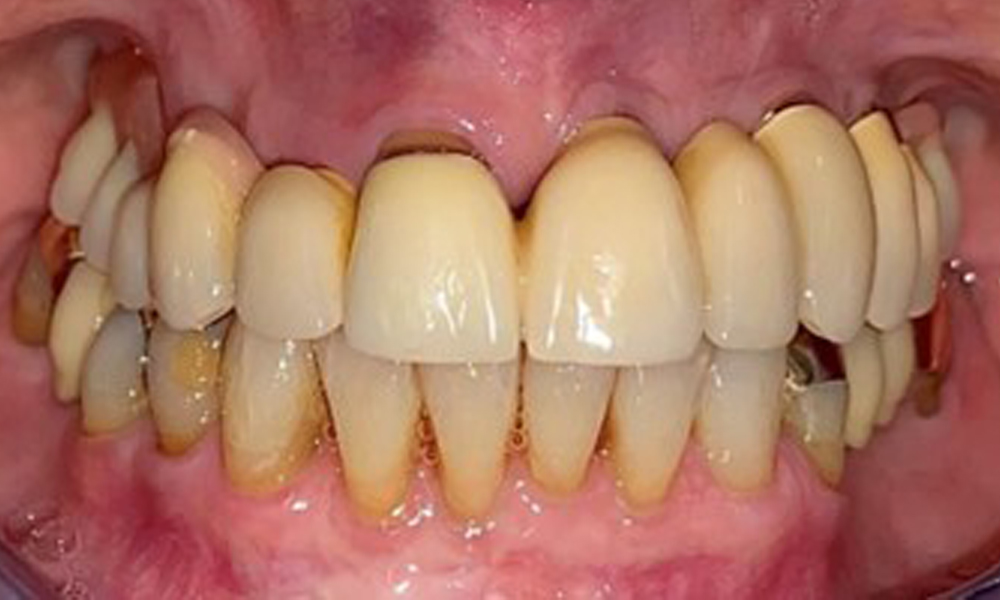

Frontal view with the maxillary denture in situ.

Fig. 1: Frontal view with the maxillary denture in situ.